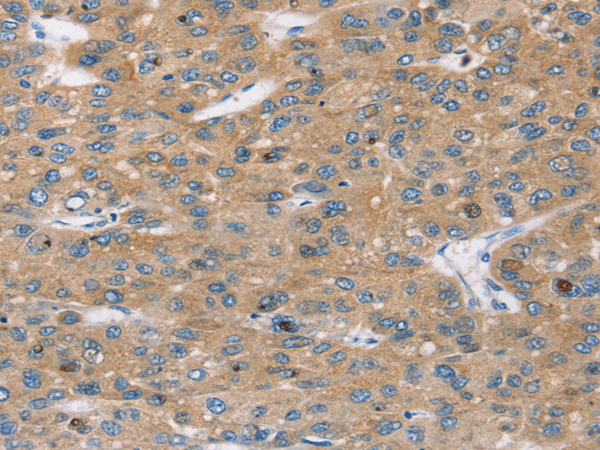

分类: 科研抗体货号: P10652别名:应用: WB,IHC反应种属: Human, Mouse

分类: 科研抗体货号: P10626别名: CREST; LP2261应用: IHC反应种属: Human, Mouse, Rat

分类: 科研抗体货号: P10649别名: BETA3AR应用: IHC反应种属: Human

分类: 科研抗体货号: P10625别名: AN3; MC7; DIPB; HSA249128应用: WB,IHC反应种属: Human, Mouse, Rat

分类: 科研抗体货号: P10648别名: BAR, B2AR, ADRBR, ADRB2R, BETA2AR应用: WB,IHC反应种属: Human, Mouse

分类: 科研抗体货号: P10624别名: OOMA1; PLEIAD; C5orf25应用: IHC反应种属: Human

分类: 科研抗体货号: P10646别名: C10orf22应用: WB,IHC反应种属: Human, Mouse

分类: 科研抗体货号: P10645别名: AM2; dJ579N16.4应用: IHC反应种属: Human, Mouse, Rat

分类: 科研抗体货号: P10666别名: ADTG; CLAPG1应用: IHC反应种属: Human, Mouse